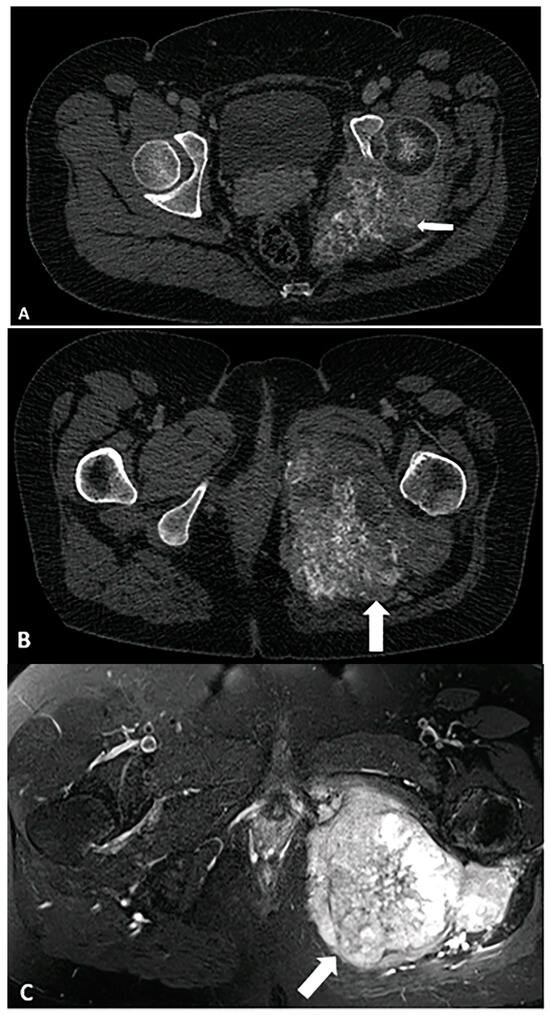

4.1. Adipocytic Tumors

- Peterson, J.J.; Kransdorf, M.J.; Bancroft, L.W.; O’connor, M.I. Malignant fatty tumors: Classification, clinical course, imaging appearance and treatment. Skelet. Radiol. 2003, 32, 493–503. [Google Scholar]

- Murphey, M.D.; Arcara, L.K.; Fanburg-Smith, J. Imaging of musculoskeletal liposarcoma with radiologic-pathologic correlation. Radiographics 2005, 25, 1371–1395. [Google Scholar]

- Henze, J.; Bauer, S. Liposarcomas. Hematol. Oncol. Clin. 2013, 27, 939–955. [Google Scholar] [CrossRef]

- Toms, A.P.; White, L.M.; Kandel, R.; Bell, R.S. Low-grade liposarcoma with osteosarcomatous dedifferentiation: Radiological and histological features. Skelet. Radiol. 2003, 32, 286–289. [Google Scholar]

- O’Regan, K.N.; Jagannathan, J.; Krajewski, K.; Zukotynski, K.; Souza, F.; Wagner, A.J.; Ramaiya, N. Imaging of liposarcoma: Classification, patterns of tumor recurrence, and response to treatment. Am. J. Roentgenol. 2011, 197, W37–W43. [Google Scholar] [CrossRef]